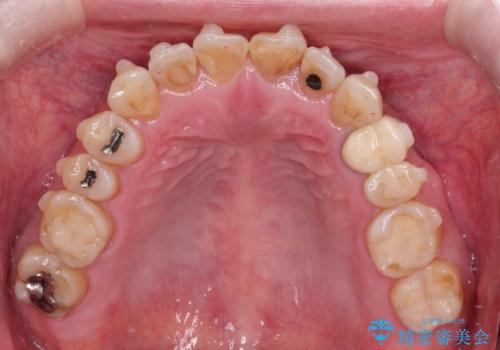

【インビザライン】前歯のガタガタを治したい

- 前歯のガタガタを主訴に来院されました。

上の歯の前突も気になってたため、奥歯の遠心移動も行いながらインビザラインにて治療を行いました。

前歯も下がり満足していただきました。

今回は奥歯の遠心移動とIPRを行って配列しています。